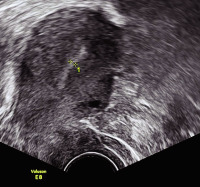

Tipps und Tricks im Gyn-Ultraschall: Das prämenstruelle und das menstruelle Endometrium

Journal für Gynäkologische Endokrinologie 2013; 7 (3) (Ausgabe für Österreich): 24-25 Journal für Gynäkologische Endokrinologie 2013; 7 (3) (Ausgabe für Schweiz): 33-34 Volltext (PDF) Abbildungen